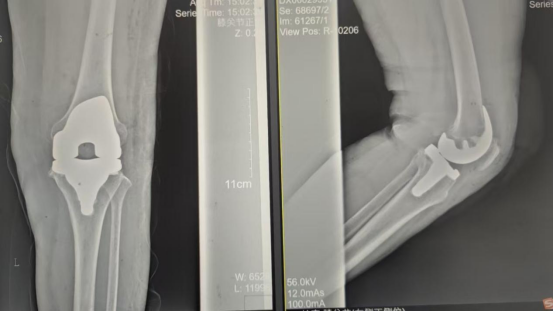

术后影像资料

因张女士患有高血压病2级(高危)、心律失常(窦缓)且伴有肺部感染等并发症。。。。。。穆志亮主任和叶龙安主治医师根据张女士的病情制定详细手术方案,,,,,,,,建议在全麻下行“左人工全膝关节置换术”。。。。。。

手术当天张女士怀着忐忑的心情进入手术室,,,,,,,,然而伴随着麻醉医师的和蔼交谈和手术护士的温馨叮咛,,,,,,,,在不知不觉中慢慢睡着,,,,,,,,手术非常顺利。。。。。。术后经医护人员的精心治疗与护理,,,,,,,,张女士康复出院,,,,,,,,最终解决了10余年的病痛。。。。。。